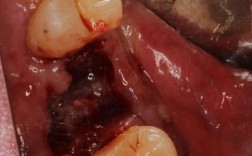

- 口腔检查: 检查缺牙区的牙龈、邻牙健康状况、咬合关系等。

- 影像学检查: 这是最关键的一步! 通常需要拍摄口腔锥形束CT,精确评估:

- 牙槽骨的高度、宽度、密度: 这是决定能否直接种植、是否需要植骨的关键。

- 缺牙区骨嵴形态: 相邻两颗牙缺,中间的牙槽骨嵴是否足够支撑种植体?